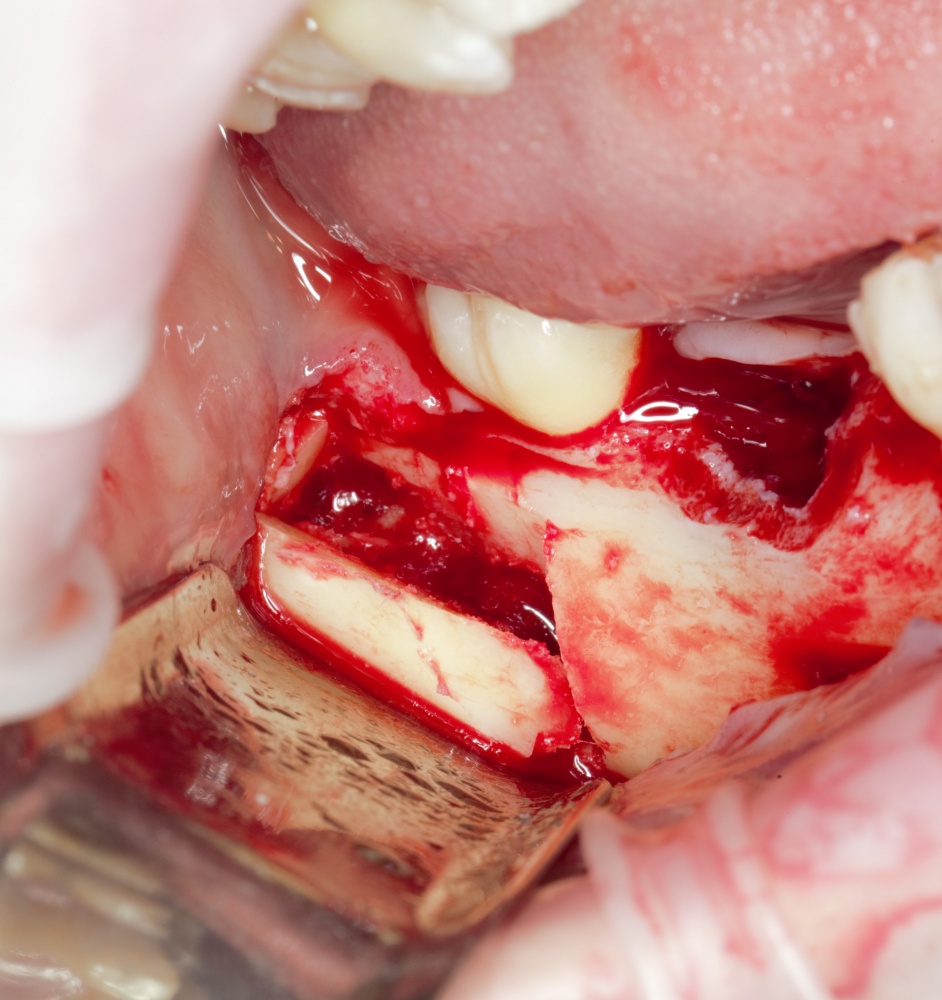

Простой. Надежный. Дешевый. Способ остеопластики.